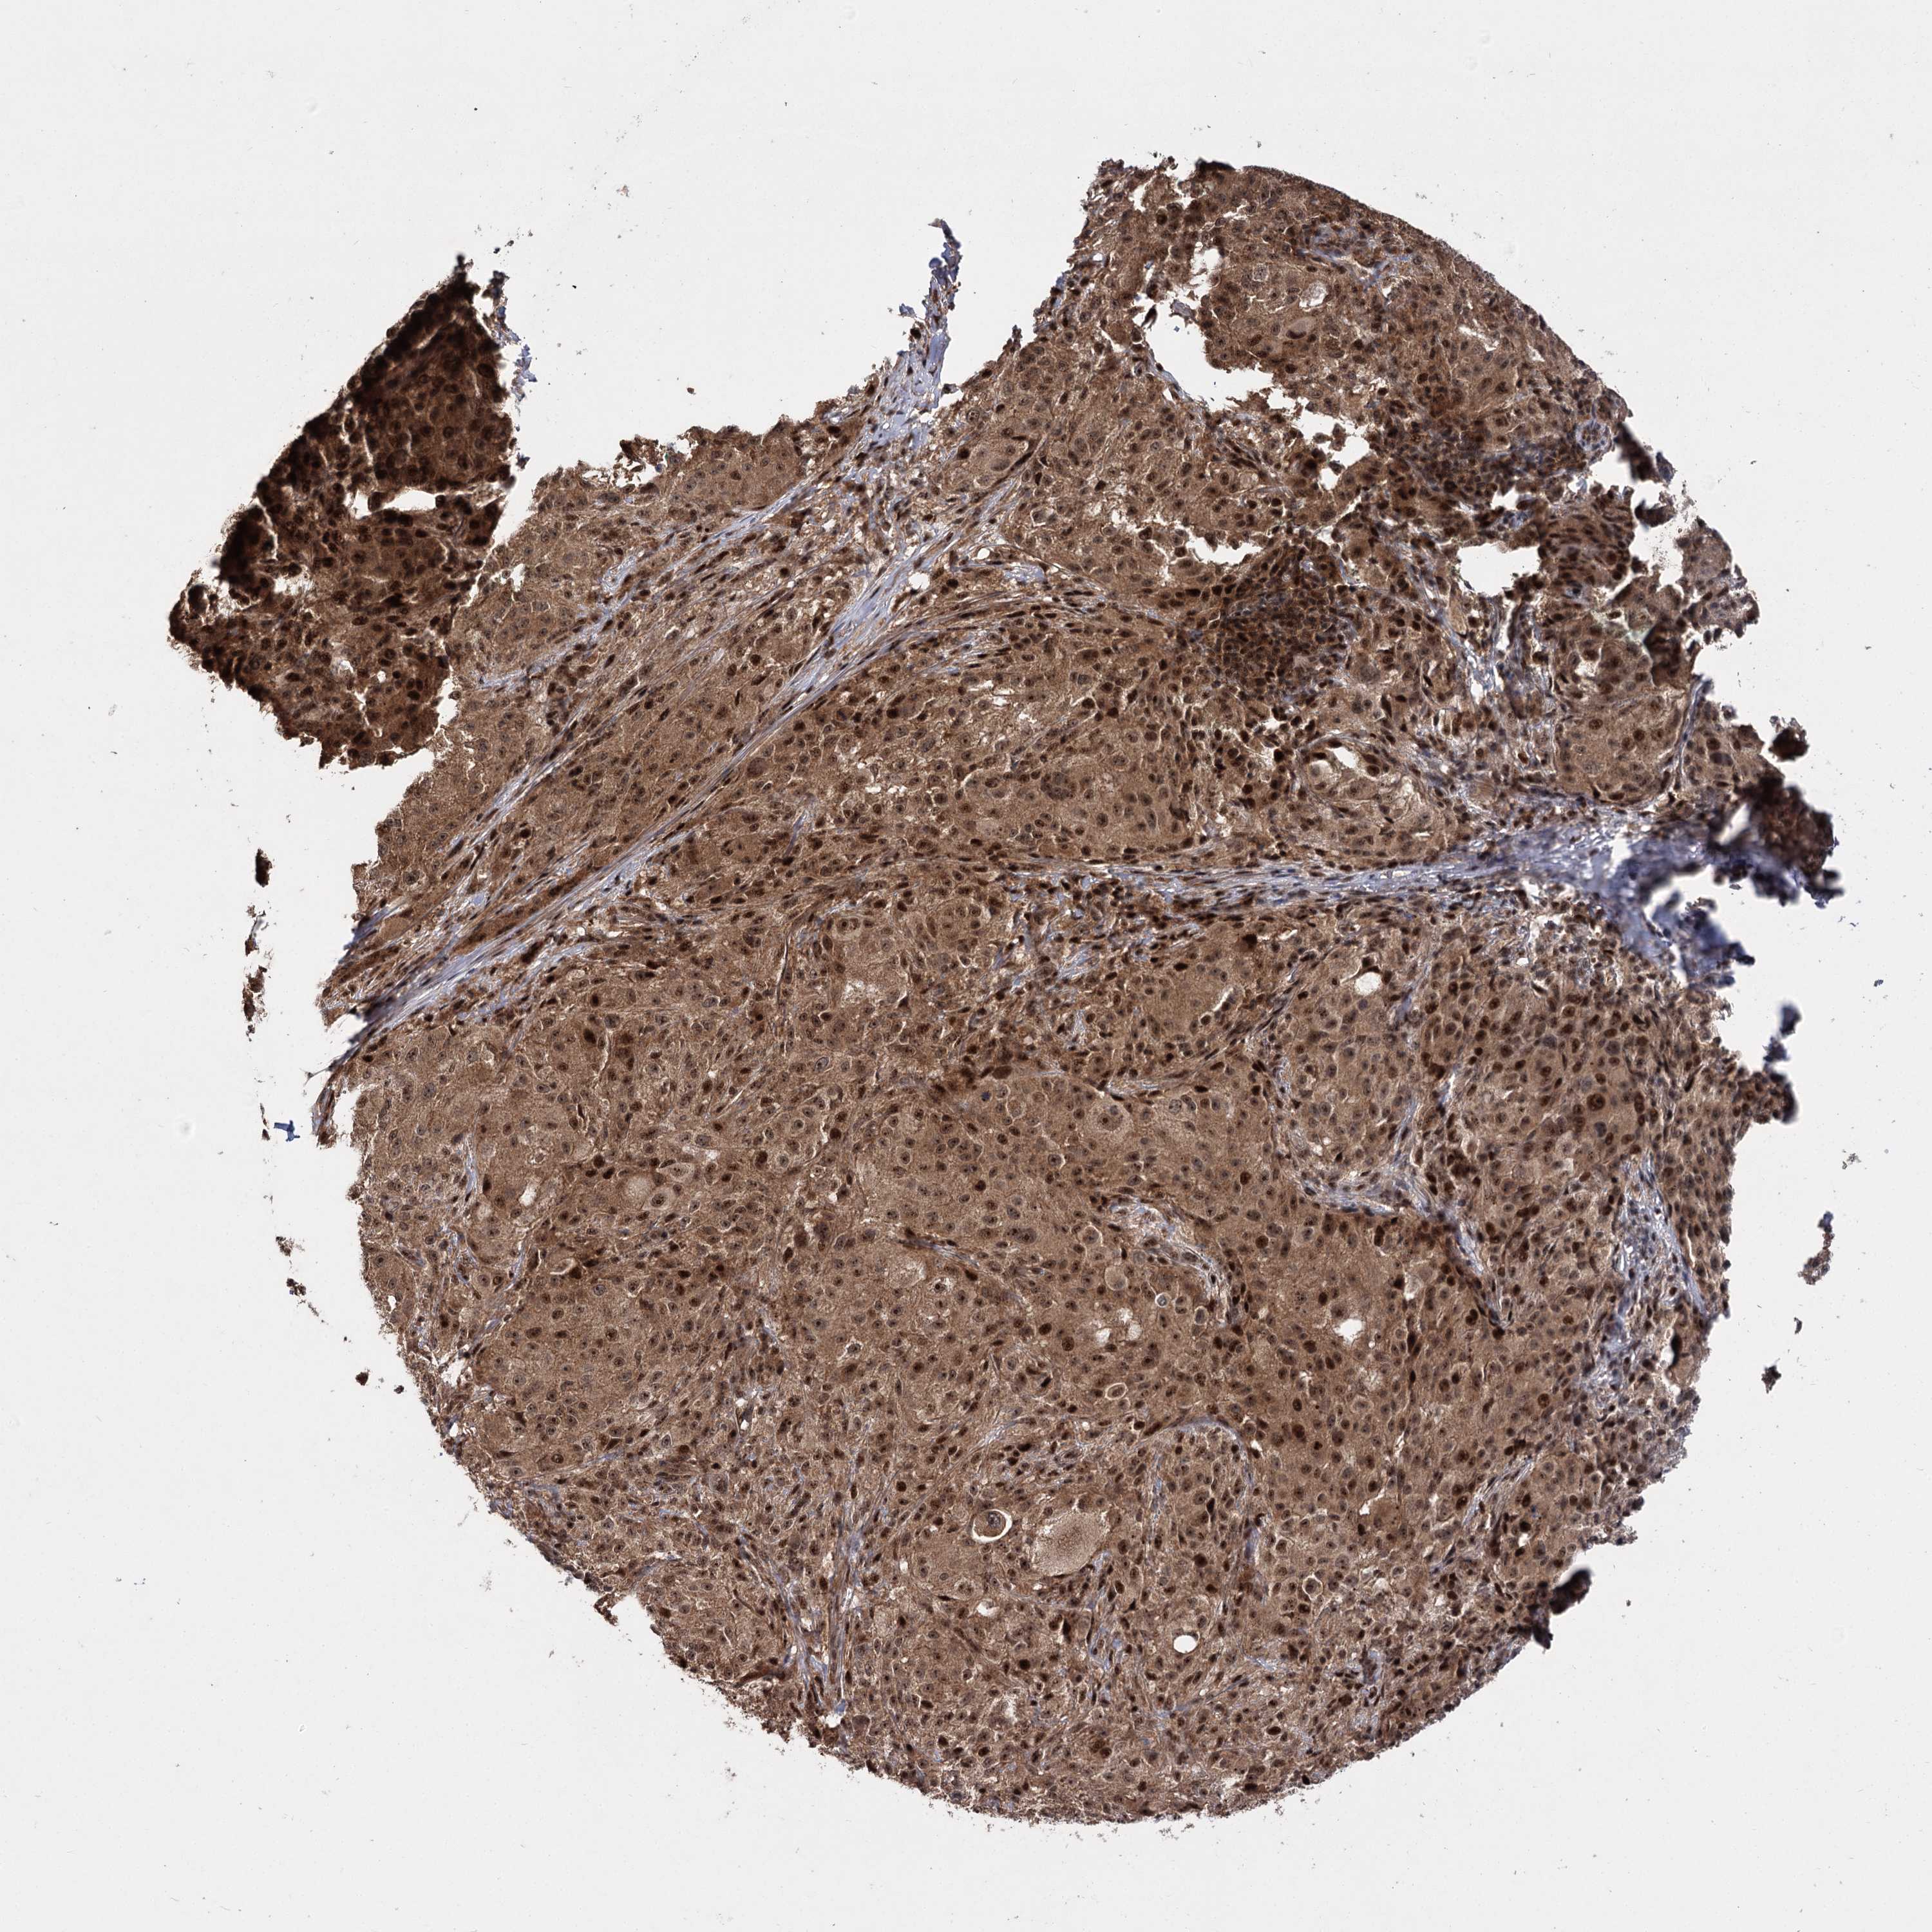

MELANOMA - Protein expressioni

A mouse-over function shows sample information and annotation data. Click on an image to view it in a full screen mode. Samples can be filtered based on level of antibody staining by selecting one or several of the following categories: high, medium, low and not detected. The assay and annotation is described here.

Note that samples used for immunohistochemistry by the Human Protein Atlas do not correspond to samples in the TCGA dataset.

Antibody stainingi

Antibody staining in the annotated cell types in the current human tissue is reported as not detected, low, medium, or high, based on conventional immunohistochemistry profiling in selected tissues. This score is based on the combination of the staining intensity and fraction of stained cells.

Each image is clickable and will lead to virtual microscopy that enables deeper exploration of all samples and also displays staining intensity scores, fraction scores and subcellular localization as well as patient and tissue information for each sample.

Antibody HPA021875

Antibody CAB037253

Staining

High

Medium

Low

Not detected

Intensity

Strong

Moderate

Weak

Negative

Quantity

>75%

75%-25%

<25%

None

Location

Nuclear

Cytoplasmic/membranous

Cytoplasmic/membranous,nuclear

Malignant melanoma, NOS

Malignant melanoma, Metastatic site